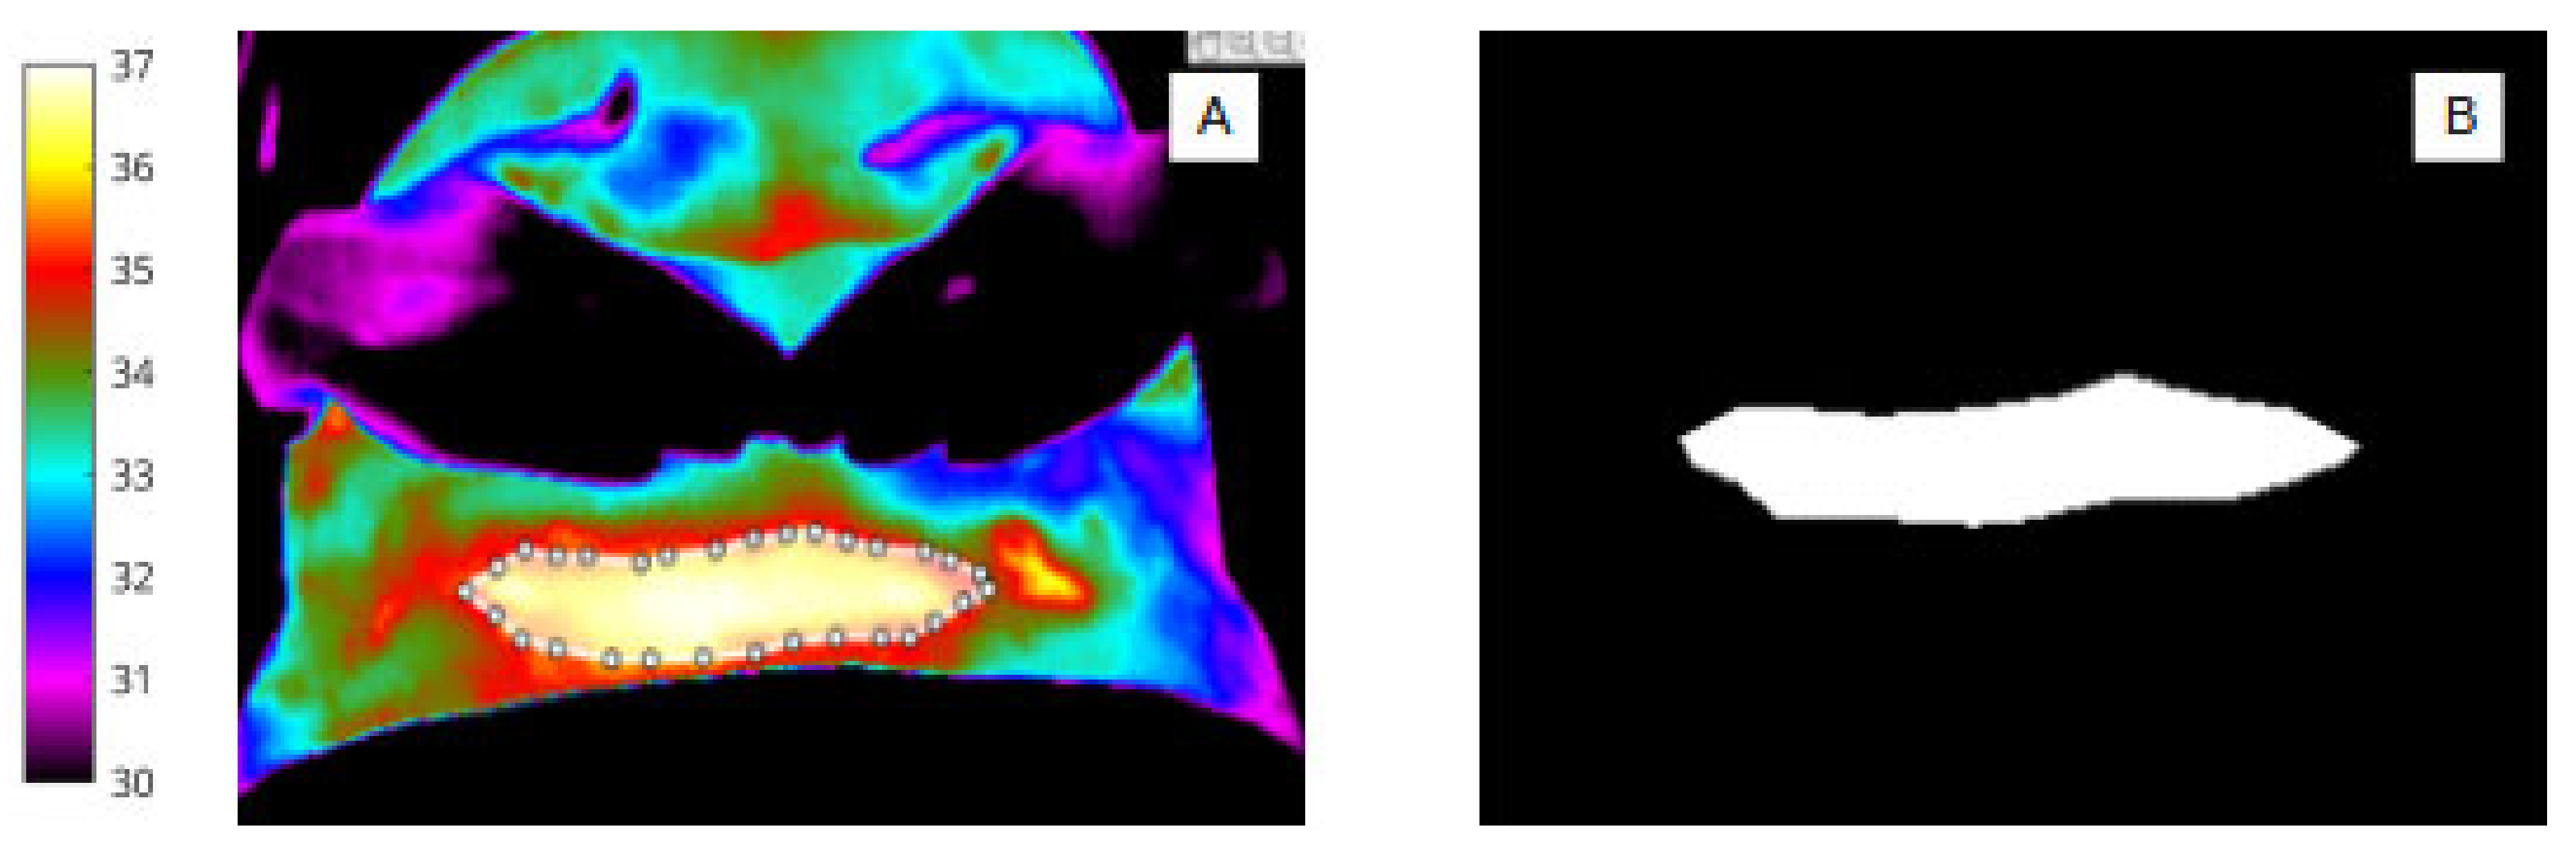

Nevertheless, it was clear from Table 2 that women who proceeded to develop an SSI had a larger number of cold spots within the wound at day 2 (by 1.07 on average) and that these cold spots covered a large area of the wound (23.92 pixels greater on average). Interestingly, the difference in number of cold spots was much lesser at day 7 (3.29 for women who developed an SSI vs. 2.79 for women who did not) and the number of cold spots was nearly the same at day 15 (2.69 for patients who developed an SSI vs. 2.39 for patients who did not). However, whilst the descriptive statistics in Table 2 indicated that the number and extent of cold spots within the wound might have predictive capability, univariate logistic regression analysis of each of these features was inconclusive for this sample size studied. An example is included here, in Figure 10.

Figure 10.

Cold spots in the wound site at day 2 of a woman who proceeded to develop SSI after caesarean section (A) and a woman with an uncomplicated wound recovery period (B).

With regard to feature extraction from within the wound area, thermal cold spots representing low temperature features were present; the pixel area of cold spots was greatest at day 2 for those who later developed SSI.